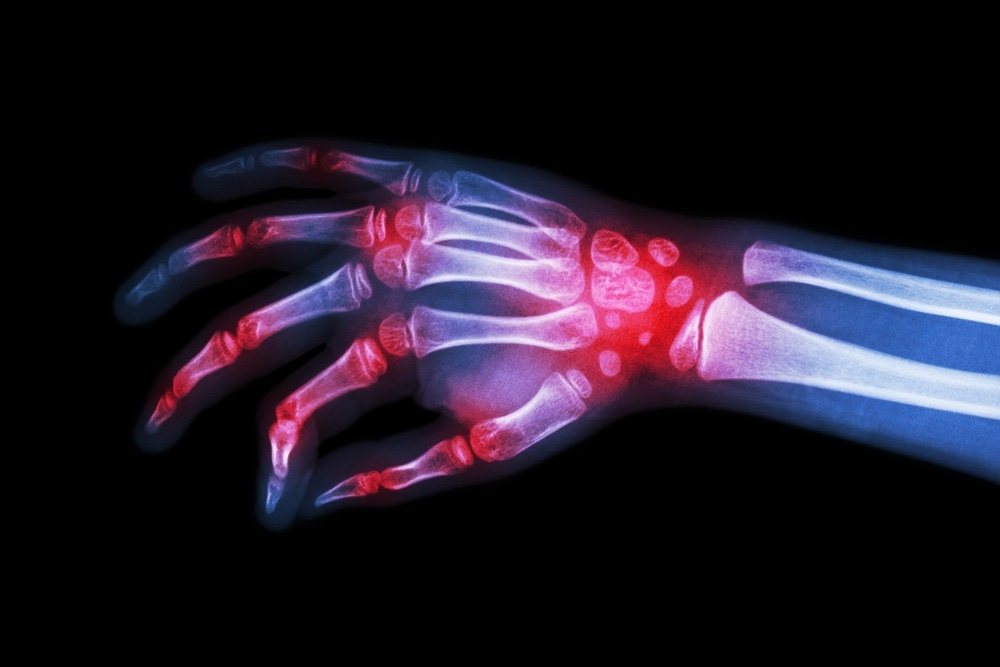

rheumatoid arthritisImage Credit: Puwadol Jaturawutthichai / Shutterstock.com

The inflammation in the joint primarily affects the synovium, the smooth lining of the joint cavity and bone ends, that produces lubricating fluid. As a result, the synovium swells and becomes painful, leading to joint stiffness. The small hand and foot joints are most frequently involved, with a symmetrical pattern. The eventual outcome with severe or inadequately controlled RA may be the erosion of the joints and deformity.